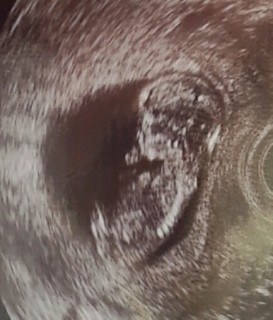

右腕を上げて両足をぴこぴこ動かしてました。 この日、初めての女性の先生に見てもらって「わ!可愛い」と言ってもらえたのがすごく嬉しかったのを覚えています

指が可愛い♡